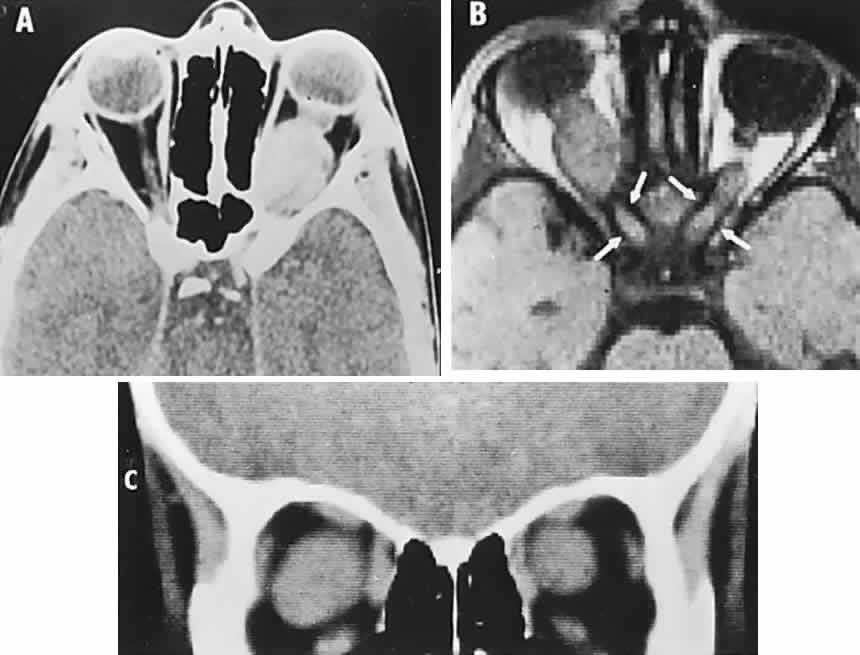

Diseases and pathologic alterations involving the retina provoke the least clinical dilemma in that, for the most part, the ophthalmoscope resolves the question of the anatomic level at which the visual pathways are involved. The problem of complicated neurodiagnostic studies should not arise, although fluorescein angiography, electroretinography (ERG), and other retinal function tests (see Volume 2, Chapter 2) may prove valuable. There are two major pitfalls to be avoided. First, minimal retinal changes may be misconstrued as the cause of disproportionately perturbed visual function, or a normal macula may be misinterpreted as abnormal. For example, a patient with relentless monocular visual loss, a central field depression, and afferent-defect pupil, with a few drusen or minimal derangement of retinal pigment epithelium at the fovea, must not be dismissed with an inappropriate diagnosis of “macular degeneration.” In this instance, the afferent-defect pupil indicates a conductive lesion of the optic nerve and cannot be attributed to minimal retinochoroidal disease. Second, true macular disease, especially when bilateral and ophthalmoscopically subtle, should raise the question of macular dystrophies that masquerade as neurologic disease or for which no cause is apparent (Fig. 1). Indeed, there are increasing numbers of retinal disorders that produce subtle or even insignificant objective fundal changes that may escape conventional ophthalmoscopic detection.

Fig. 1. A 14-year-old boy referred for occult neurologic disease or malingering who had undergone magnetic resonance imaging and psychiatric counseling. Visual acuity was 20/100 in both eyes. Fundi (A and B) show thinned rounded macular reflexes and mild pigment changes at the foveae. Fluorescein angiography (C) disclosed marked macular pigment epithelial disturbance. Diagnosis: juvenile macular degeneration (Stargardt's type).